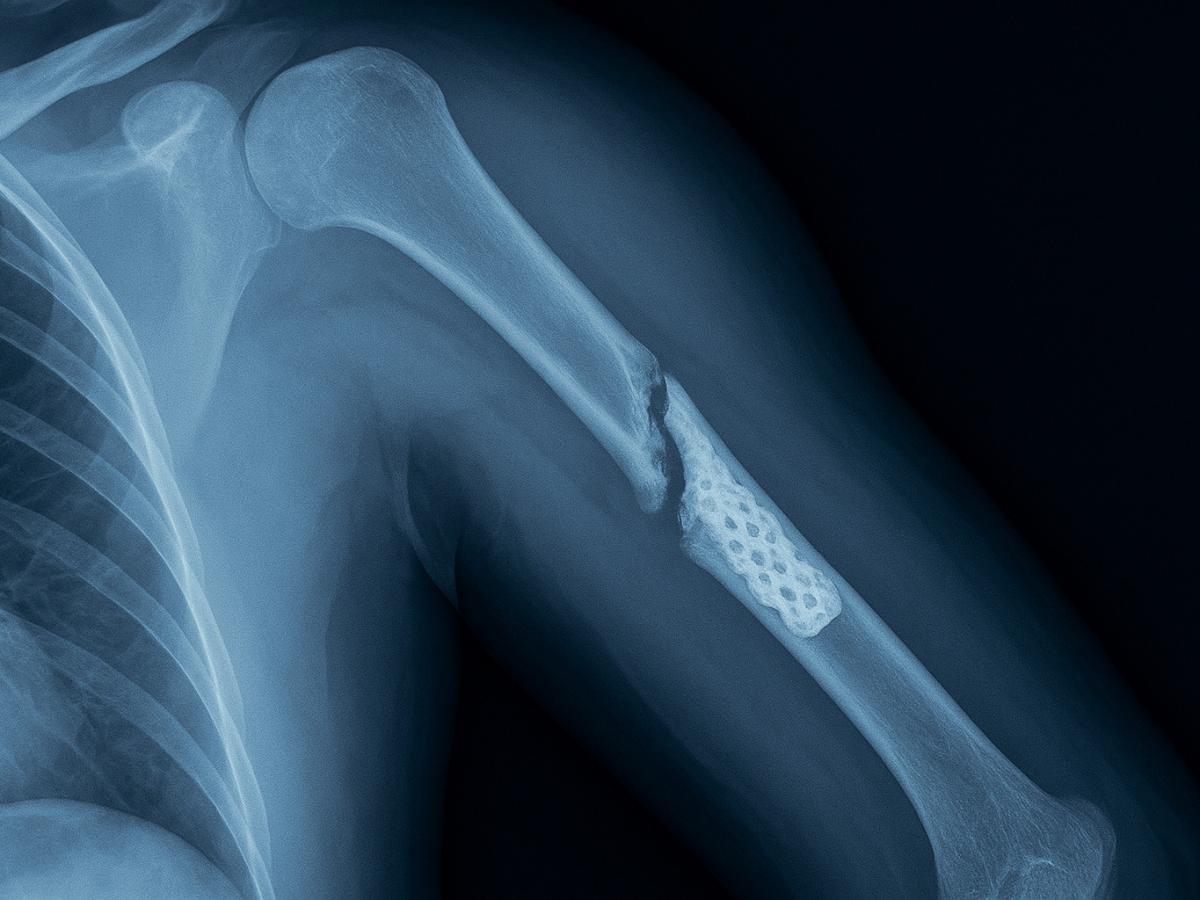

Рентген с 3D-имплантатом

Кости ломаются не от старости, а от бездействия: врачи предупредили о скрытой угрозе

Остеопороз — одно из самых коварных заболеваний костной системы, которое долгое время может протекать без симптомов. Всемирный день борьбы с ним ежегодно напоминает: здоровье костей требует внимания, особенно у людей старшего возраста.

По словам главного врача челябинской областной клинической больницы №2 Максима Угнивенко, болезнь чаще всего обнаруживается уже после перелома — и зачастую травма оказывается куда серьёзнее, чем кажется на первый взгляд.